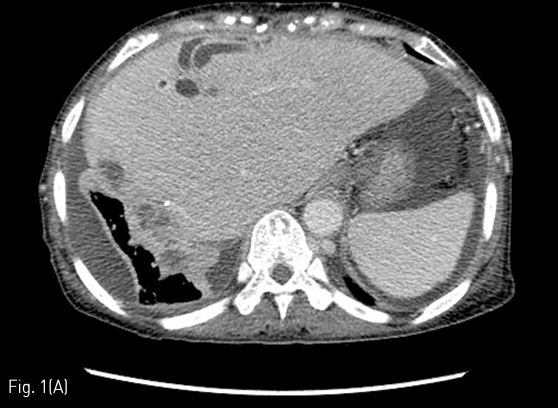

전산화 단층촬영에서 간우엽절제부-장문합부에 재발암의 침범이 있으며 이 병변이 우측 횡격막 및 폐실질을 침범하고 이와 동반된 폐농양이 폐우하엽에 보였다 (Fig. 1A-B).

64-year-old woman with fever, biliptysis and dyspnea. An axial CT scan shows recurred tumor along resection margin of left lobe of liver and dilated bile ducts (A), and a lung abscess in right lower lobe (B).